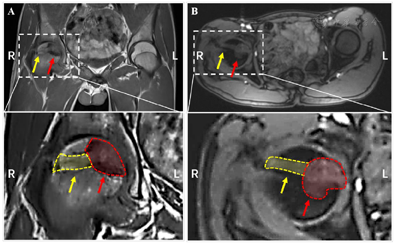

右髋关节CT及核磁:右侧股骨头骨骺内类圆形骨质破坏影,病灶边缘见硬化边。局部骨皮质变薄、缺损,股骨头内可见低密度孔道影,股骨头穿刺术后改变,股骨头近端及髋臼骨髓水肿,髋关节腔积液,滑膜增殖显著(图1)。